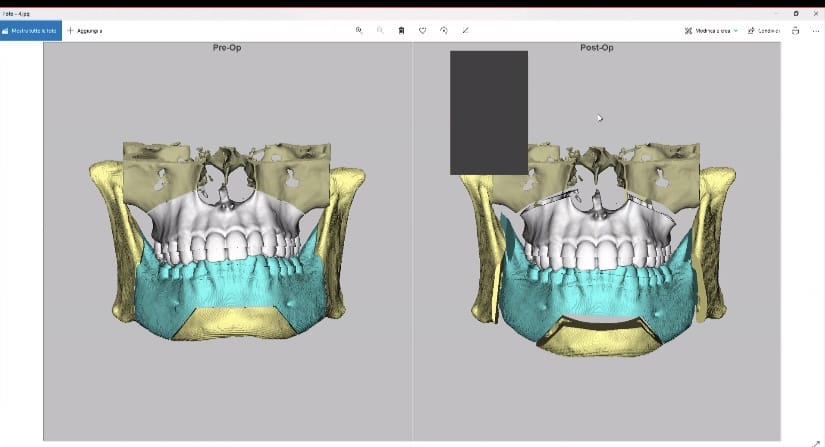

My surgeon plan:

4mm downgraft in total of the lower third

4mm anterior downward custom wedge shaped genio

3 mm posterior genio

10mm ramus widening - 5mm each sided

a combo of clockwise and counter clockwise rotation to fix my canted mandible

3mm of lefort 1